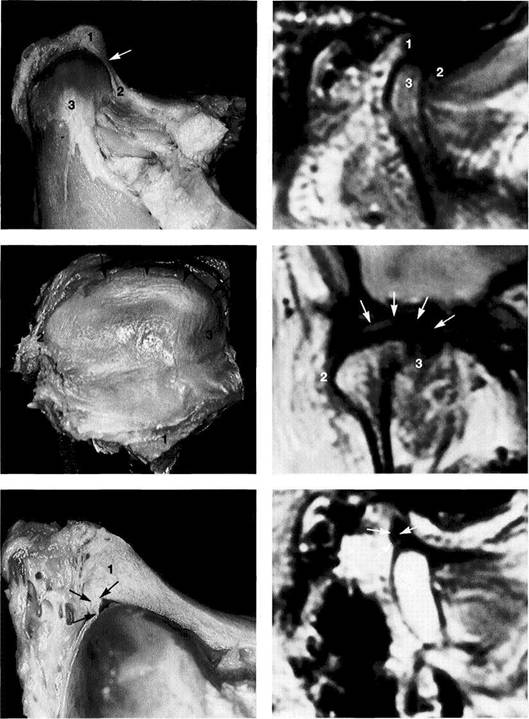

Normal joint

Left: Macroscopic anatomical pre­paration of a right temporo­mandibular joint with normal disk position. The pars posterior (1), pars anterior (2), pars media (arrow), and condyle (3) can be clearly seen.

Right: In spite of the reduction in signal caused by formalin fixation, the corresponding slice in MRI shows the identical relationships between the disk (1,2) and condyle

Medial disk displacement

Left: Formalin-fixed preparation from a right joint. In this anterosu-perior view, the displacement of the disk (arrows) toward the medial is evident.

Lateral pterygoid muscle

Lateral pole

Medial pole

Right: MRI in the angled coronal plane confirms the medial disk po­sition (arrows). The contours of the fossa and condyle are reproduced precisely.

Shape of the pars posterior

Left: Macroscopic anatomical pre­paration of a right articular disk showing its positional relationship to the condyle. The posteroinferior edge of the pars posterior (1) shows a small triangular area of fi­brosis (arrows).

Right: In spite of the sharply re­duced signal emission resulting from formalin fixation, even this type of change is accurately repro­duced (arrows). Here the use of a combination of T1 and T2 weight­ing is often helpful.

Reproduction of Anatomical Detail in MRI

Fibrosis of the bilaminar zone

Left: Formalin-fixed preparation of the centromedial part of a left tem­poromandibular joint with localized fibrosis of the bilaminar zone (ar­rows).

Pars posterior

Right: The MRI accurately repro­duces the abnormality (arrows) dis­tal to the flattened pars posterior. The contour of the condyle is indi­cated by a broken line.

Presumed "posterior disk displacement"

Left: Macroscopic preparation of a left temporomandibular joint with normal positioning of the pars an­terior (1) and pars posterior (2) in the lateral portion of the joint. The retrodiskal structures appear thick­ened.

Right: In an MRI there appears at first glance to be a posterior disk displacement (arrows). Under clos­er inspection, however, it can be seen that the pars anterior (1) and pars posterior (2) lie in correct rela­tion to the condyle.

Left: A view of the disk and the bil­aminar zone after further prepara­tion again reveals the correct posi­tional relationships. Here the pars anterior (1) and pars posterior (2) can be identified more readily. The presumed "posterior disk displace­ment" is a false positive interpreta­tion of the fibrosis of the bilaminar zone (arrows).

Right: MRI of the same joint shown in Figure 427.

Disk perforation and osteoarthrosis

Left: Anatomical preparation of a left temporomandibular joint with arthrotic changes (black arrows) and extensive disk perforation (white arrows). In the anterior re­gion only a part of the former pars anterior (1) can still be recognized.

Right: MRI shows similar conditions. The cortical layer of the arthrotic condyle is thickened extensively (arrows). The remainder of the pars anterior (1) can still be distin­guished.